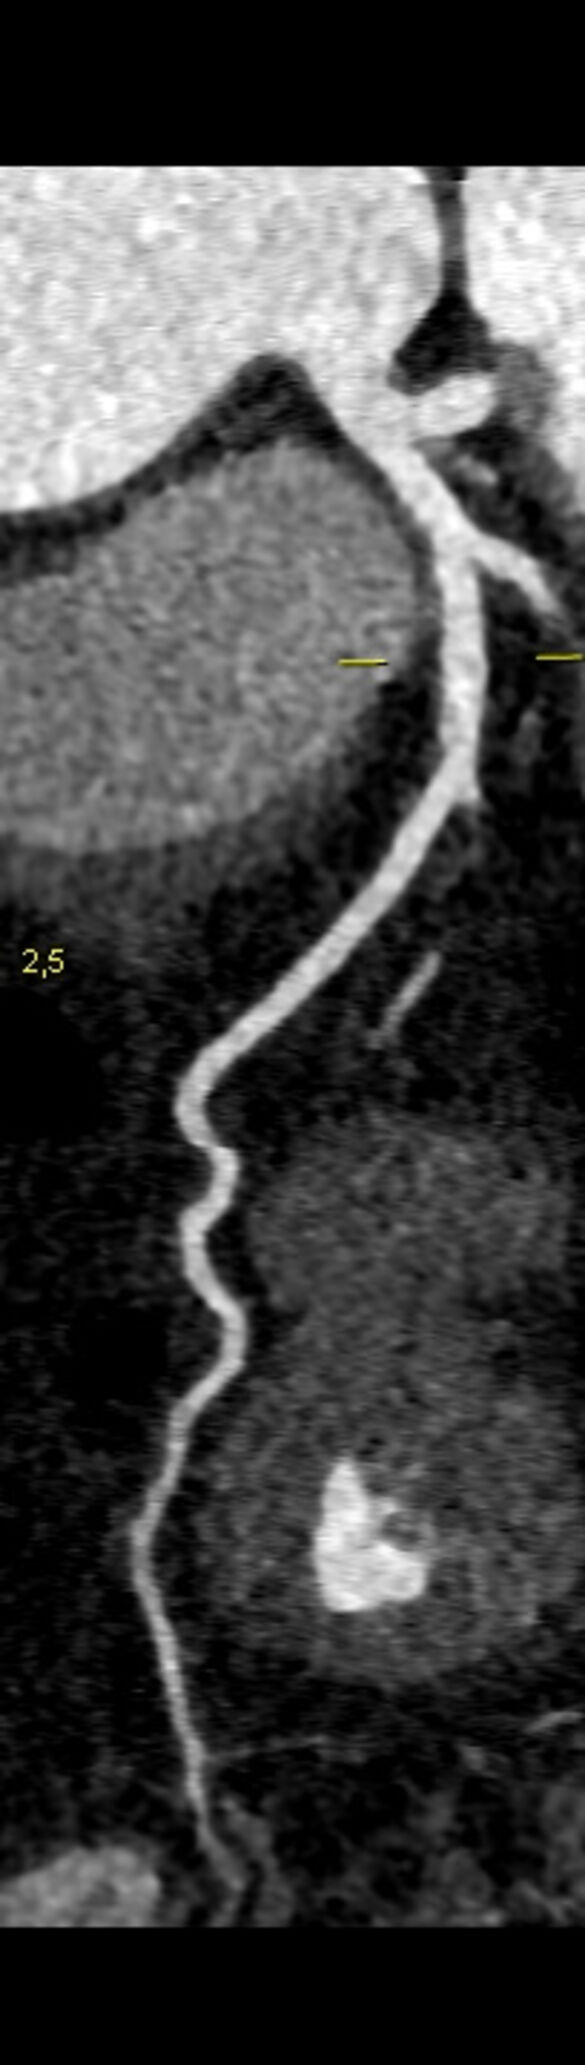

„Mit dem neuen Computertomographen steht uns nun auch die Möglichkeit zur Verfügung, Patienten nicht-invasiv am Herzen zu untersuchen. Herzkranzgefäße können durch das Herz-CT auf Engstellen und Herzkranzgefäßverkalkungen untersucht werden. So kann in ausgewählten Fällen eine Herzkatheteruntersuchung über die Leiste oder dem Arm durch ein Herz-CT vermieden werden. Die Behandlung wird für unsere Patienten so angenehm und auch risikoarm.“

„Neben den konventionellen 2D-Daten wird auch ein 3D-Modell des Herzens zur besseren Veranschaulichung erstellt,“ sagt Baumann. Der abschließende Befund würde in der Regel noch am selben Tag erstellt und dem behandelnden Arzt zugeschickt.

Darstellung Koronararterie